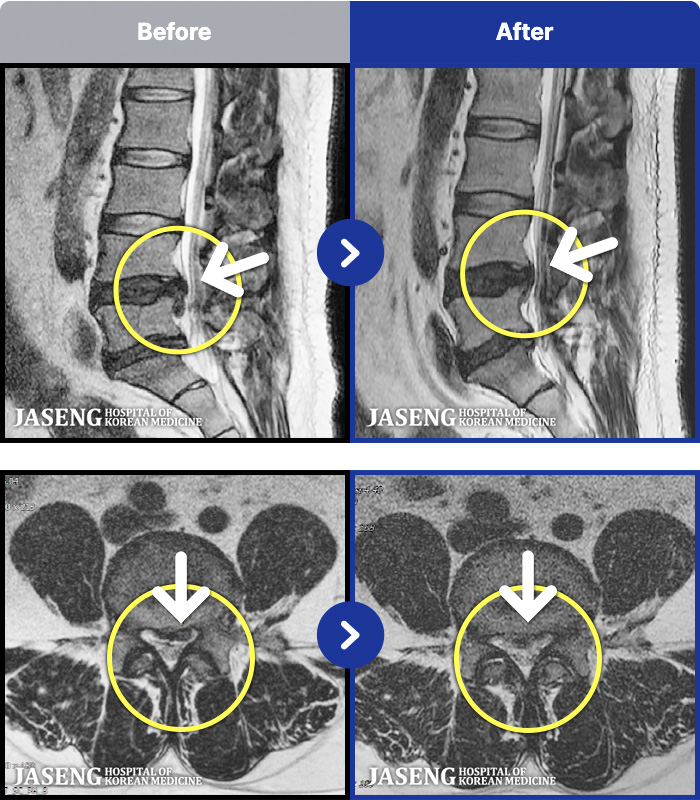

MRI ġ

MRI ũ ʸ Ȯϼ.